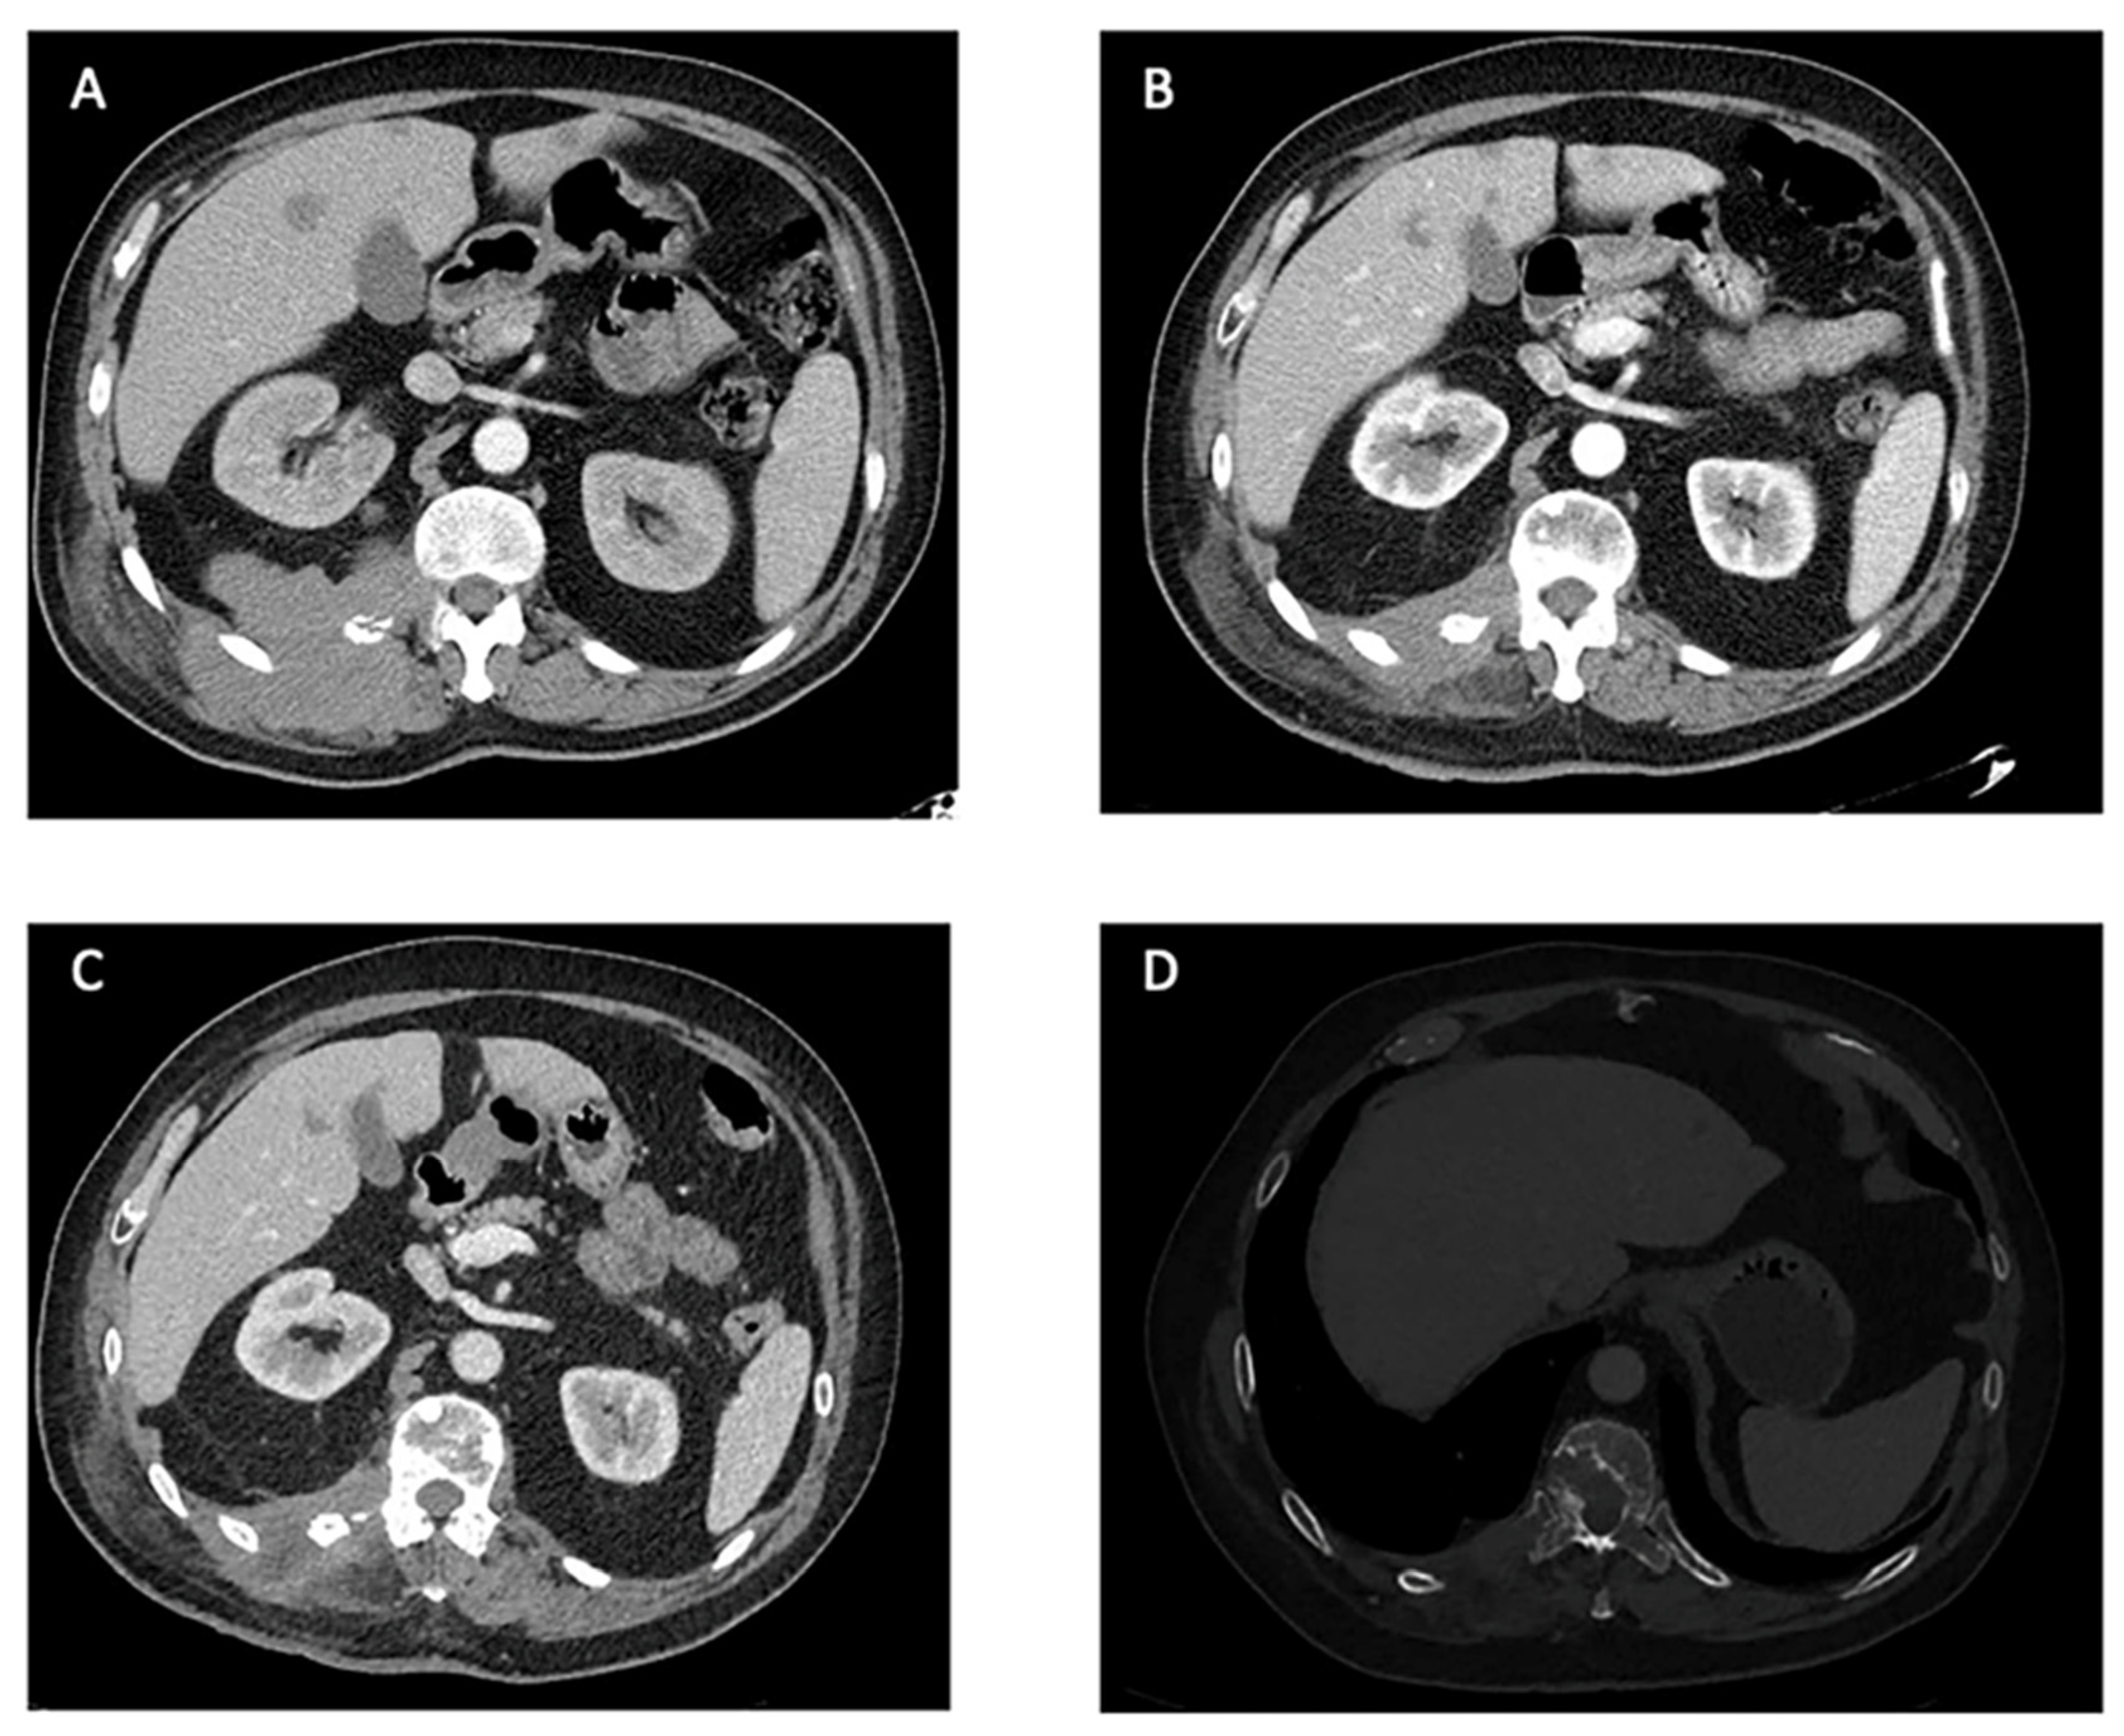

| Karasavvidou, 2023 [40] | Urethra | Lung, pelvis | None | First | 10 months | SD | * | - |